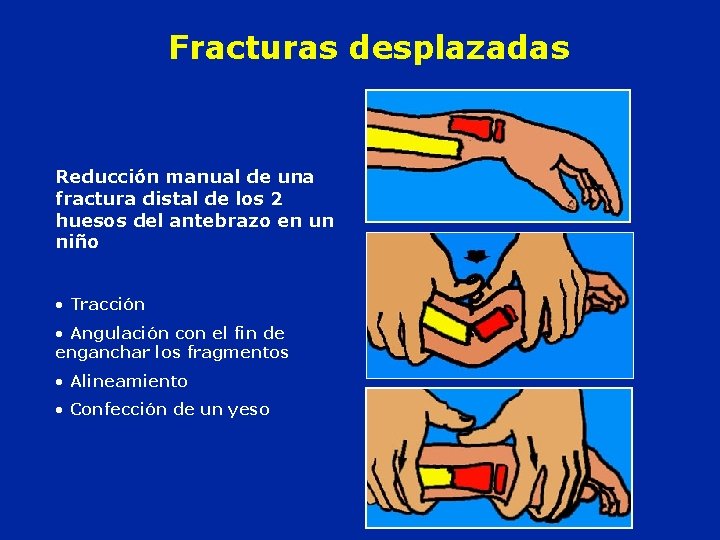

Fracturas desplazadas Reducción manual de una fractura distal de los 2 huesos del antebrazo en un niño • Tracción • Angulación con el fin de enganchar los fragmentos • Alineamiento • Confección de un yeso